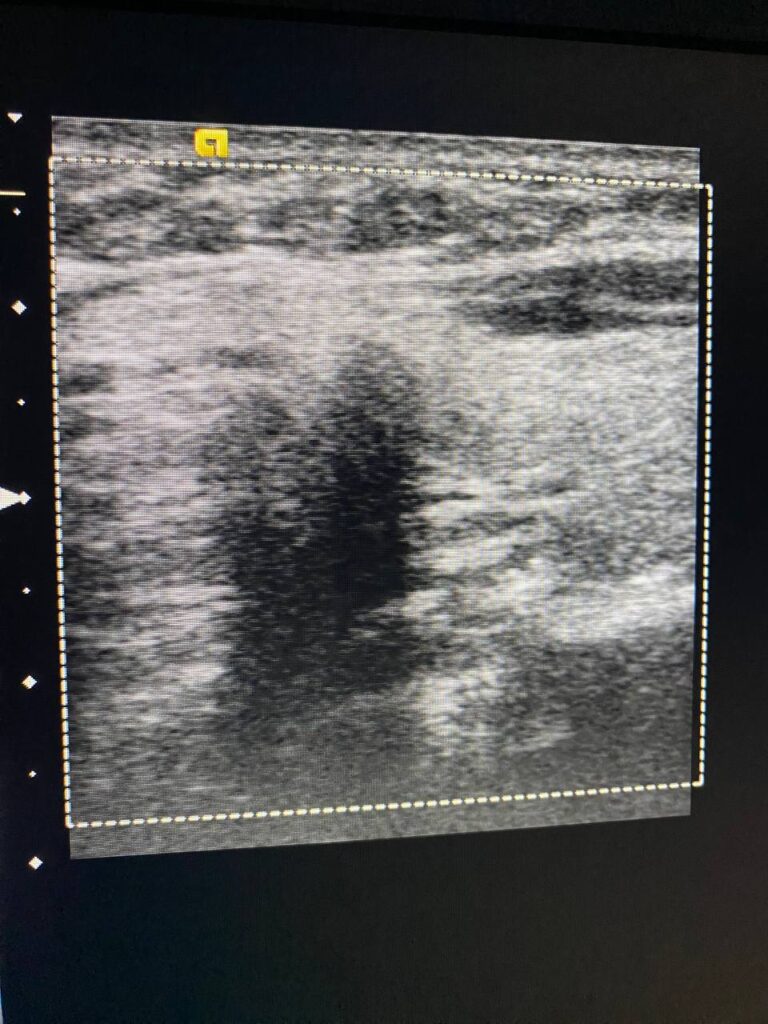

in the left sided of the isthmus presence of two hypoechoic masses , size 3.2×3.3mm, it has indistinct margin , suspicious nodule can not be exclude for further study , the other mass 3.6×2.4mm more regular , mostly lymph node , please for further study TIRADS U4